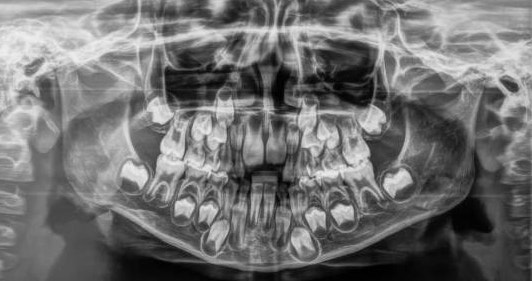

유치의 뿌리 밑에는 나중에 나오기 위해 준비하고 있는 영구치의 치배(치아싹)이 위치하고 있습니다. 우리가 치과에 가서 파노라마 엑스레이 사진을 찍어보면 어린 아이들의 경우 치아가 위아래로 여러개 있는 것처럼 보이는데 이것이 바로 유치 아래 위치한 영구치 치배들입니다.